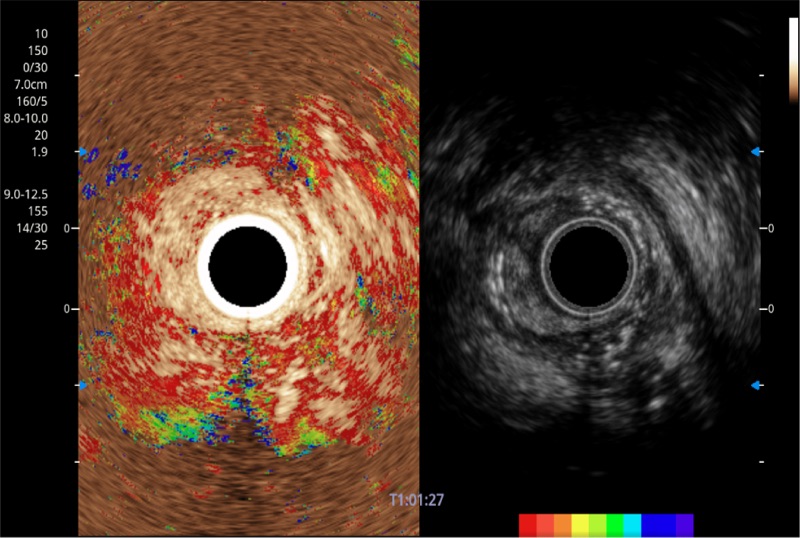

清晰显示胆总管及周围血管分布

可人为将灰阶图像转变成彩色的显示方式,增强人眼对于不同回声强度的敏感度,主观上增加了图像分辨率